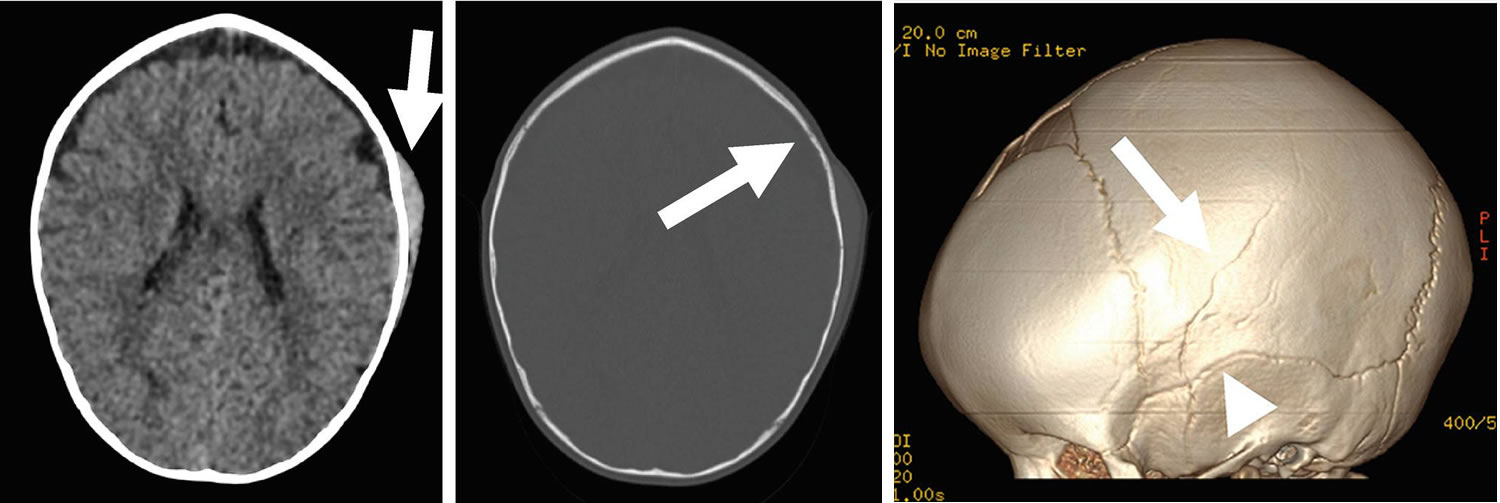

Figure 10. Cephalohematoma in adult

Footnotes: Axial non-contrast head CT demonstrating a small left parietal scalp hematoma (left image, arrow) associated with a subtle underlying non-displaced left parietal bone fracture (center image, arrow) in a young child. 3D volume rendered reconstructions, which increase sensitivity for identifying non-displaced fractures, better depict the linear left parietal bone fracture (right image, arrow) that extends through the left squamosal suture (right image, arrowhead). No intracranial hemorrhage was present.